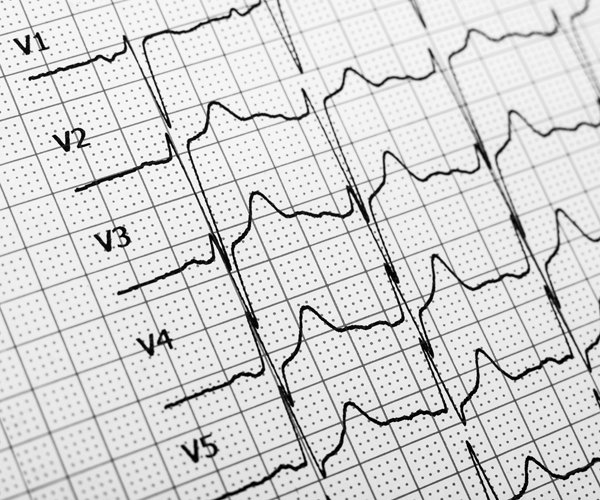

С повышением уровня глюкозы в кровеносном русле стенки сосудов становятся очень хрупкими, что повышает вероятность ишемического инсульта. При диабете, помимо регулярного измерения давления, рекомендуется систематически проводить мониторинг уровня холестерина, делать раз в полгода ЭКГ и УЗИ сосудов шеи, питающих головной мозг, вовремя восполнять потерю жидкости в организме и, конечно же, строго следовать всем назначениям врача.